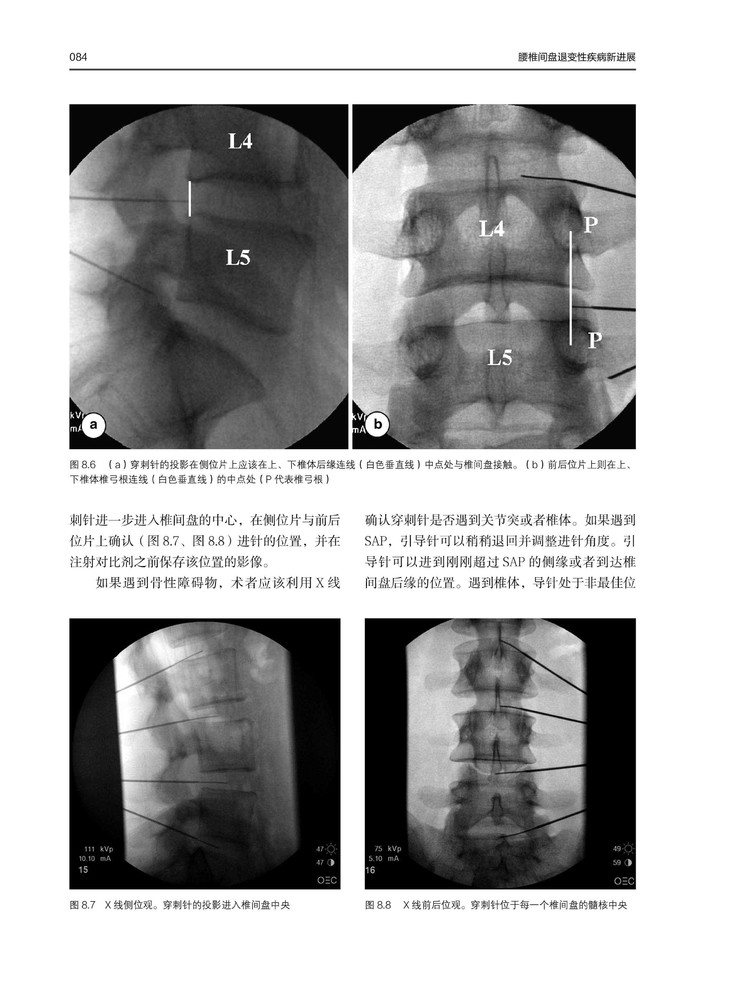

现在社会中腰椎间盘疾病患者逐年增加,本书重点介绍了腰椎间盘疾病的治疗方法,以及常见问题的解决办法。本书从物理病理学、遗传学和现代成像技术的理解等方面入手,对疾病的病因和治疗进行详细分析。同时,本书收集了大量病例,结合术图片中及术后影像学资料对病例进行分析,对临床医生工作具有参考价值。

在这本书中,脊柱领域的主要国际专家联合起来讨论了治疗腰椎间盘疾的主题、问题和方法。覆盖范围广泛,从目前从对物理病理学、遗传学和现代成像技术的理解,到各种微创性、非融合性和融合性手术技术。当接近病人并作出治疗决定时,需要仔细考虑最重要的方面。对保守治疗的作用进行了评估,并对手术技术及其适应症作了详细的描述。在总结部分,则是一些来自世界各地的顶尖专家都在反思他们在脊柱外科手术中所学到的经验教训。